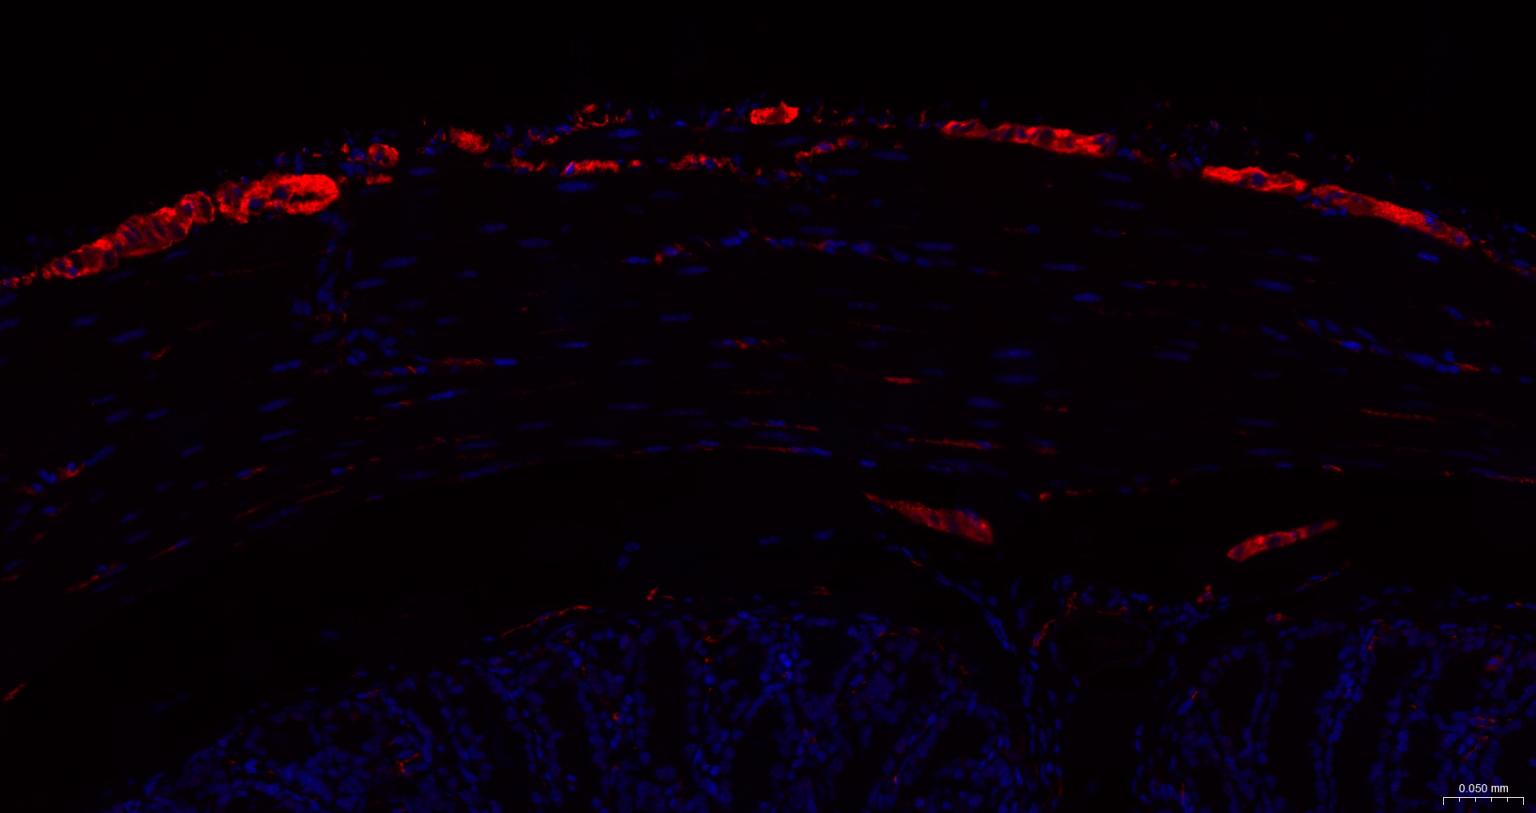

IHC-FHuman, Mouse, Rat1:50-200

IFHuman, Mouse, Rat1:50-200